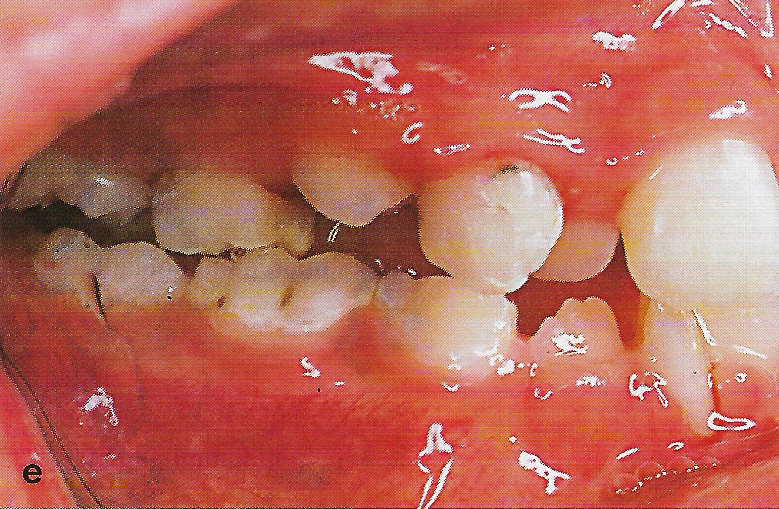

Abb. 1 a bis h Extra- und intraorale Ansicht der Patientin vor Behandlungsbeginn: Kopfbiß beziehungsweise umgekehrter Schneidezahnüberbiß und beidseitiger Kreuzbiß als Folge einer maxillären Hypoplasie sowie hälftenungleicher Mesialbiß infolge mandibulärer Verschiebung nach rechts.

• Ankylose Abb.1e

Diese Patientin war zu Behandlungsbeginn 7 Jahre alt. Sie hatte einen hälftenungleichen Mesialbiß infolge mandibulärer Verschiebung mit Kopfbiß beziehungsweise umgekehrter inzisaler Stufe, rechtsseitigem vollem Kreuzbiß und linksseitigem doppeltem Höckerbiß, maxillärer Kompression sowie Platzmangel in beiden Kiefern (Abb. 1 a bis h). Die kephalometrische Analyse ergab eine progene Kieferlagebeziehung, bedingt durch eine unterentwickelte Maxilla bei vertikalem Gesichtsschädelaufbau.